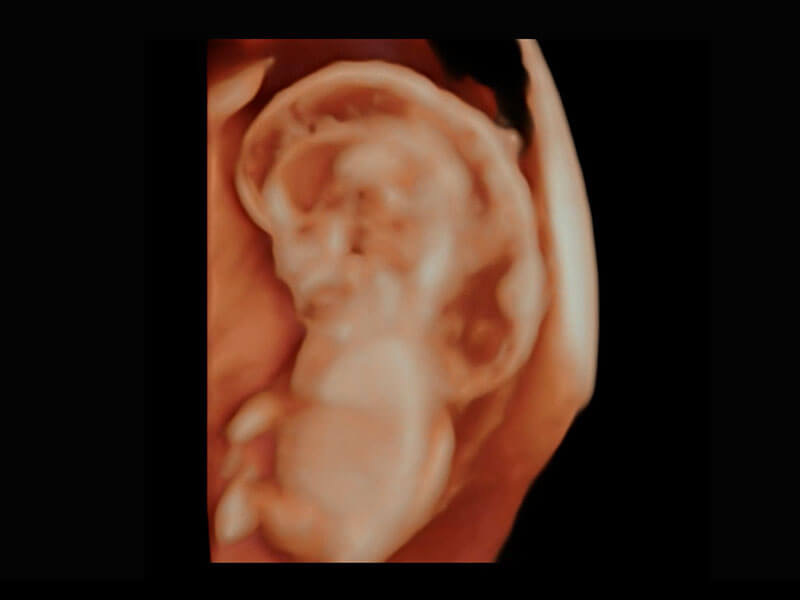

P60在胎儿早孕期超声筛查中为您带来优异的图像质量。

高分辨率容积成像-早孕胎儿

P60提供简单易学易用的高端诊断工具,为您中晚孕筛查提供快速清晰的解剖信息。

S-Fetus能够助您在实时扫查过程中自动识别标准切面、自动测量并录入报告。一个按键,即可快速、高效地获取胎儿生理指标,简化您的产科检查操作。